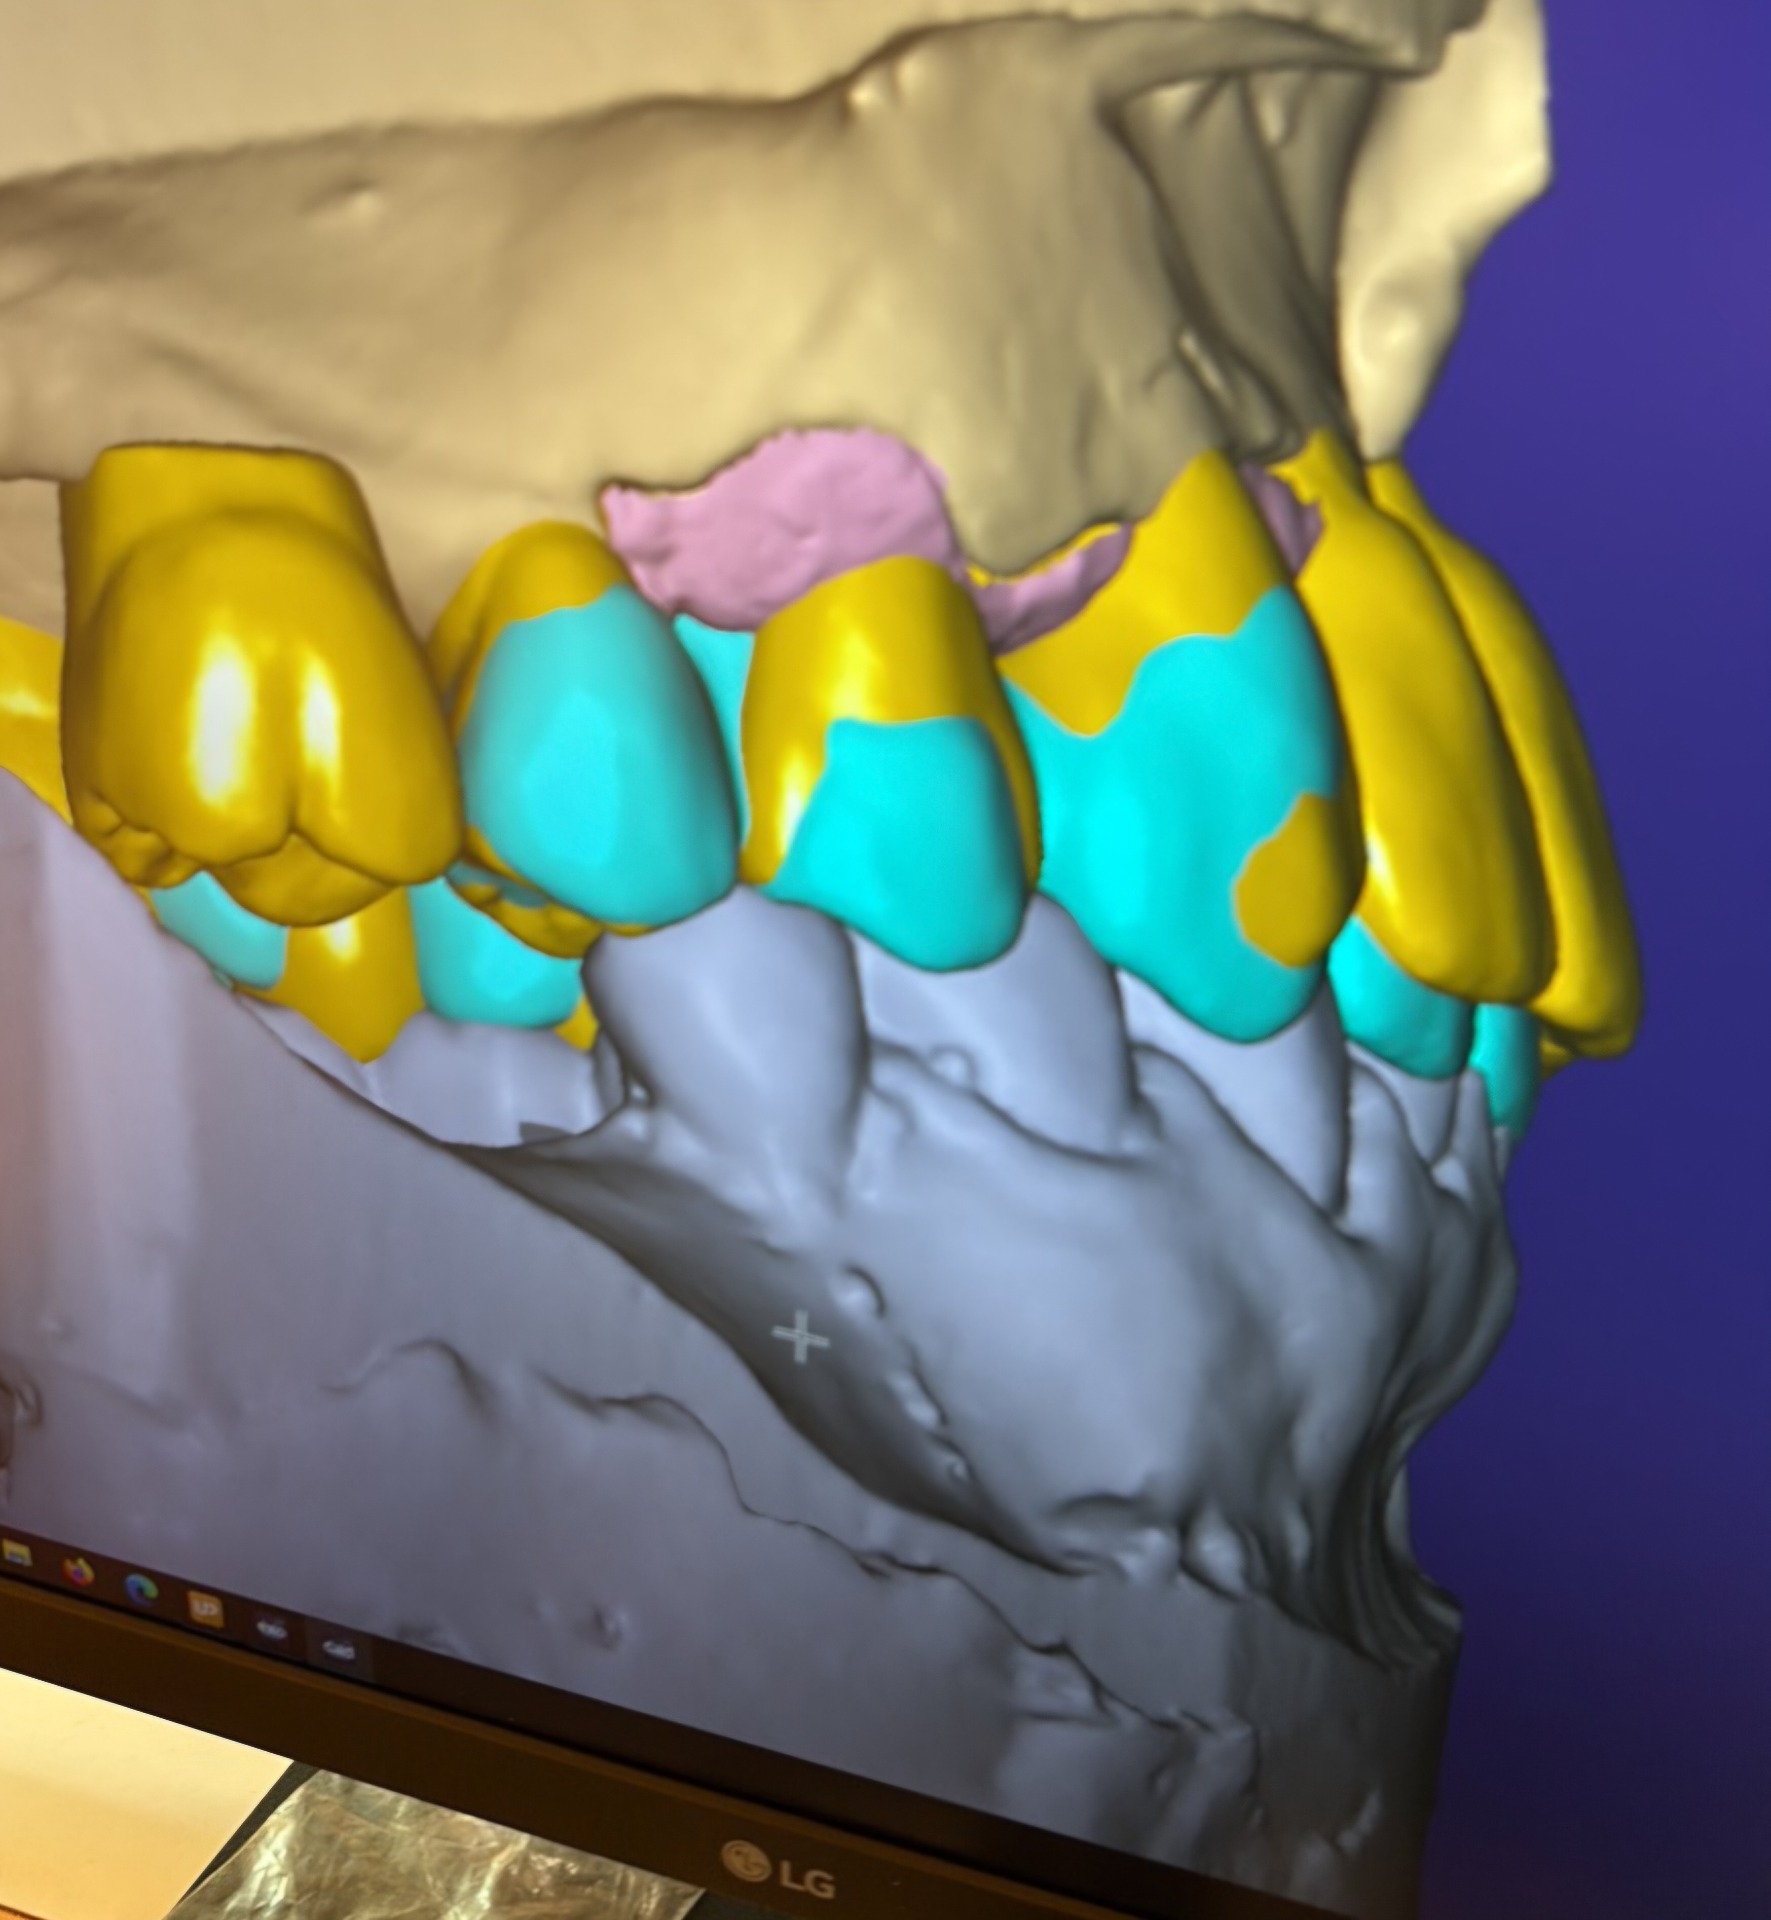

Cirkónium-kerámia, full-cirkon, fémkerámia koronák, hidak készítése digitális tervezéssel.